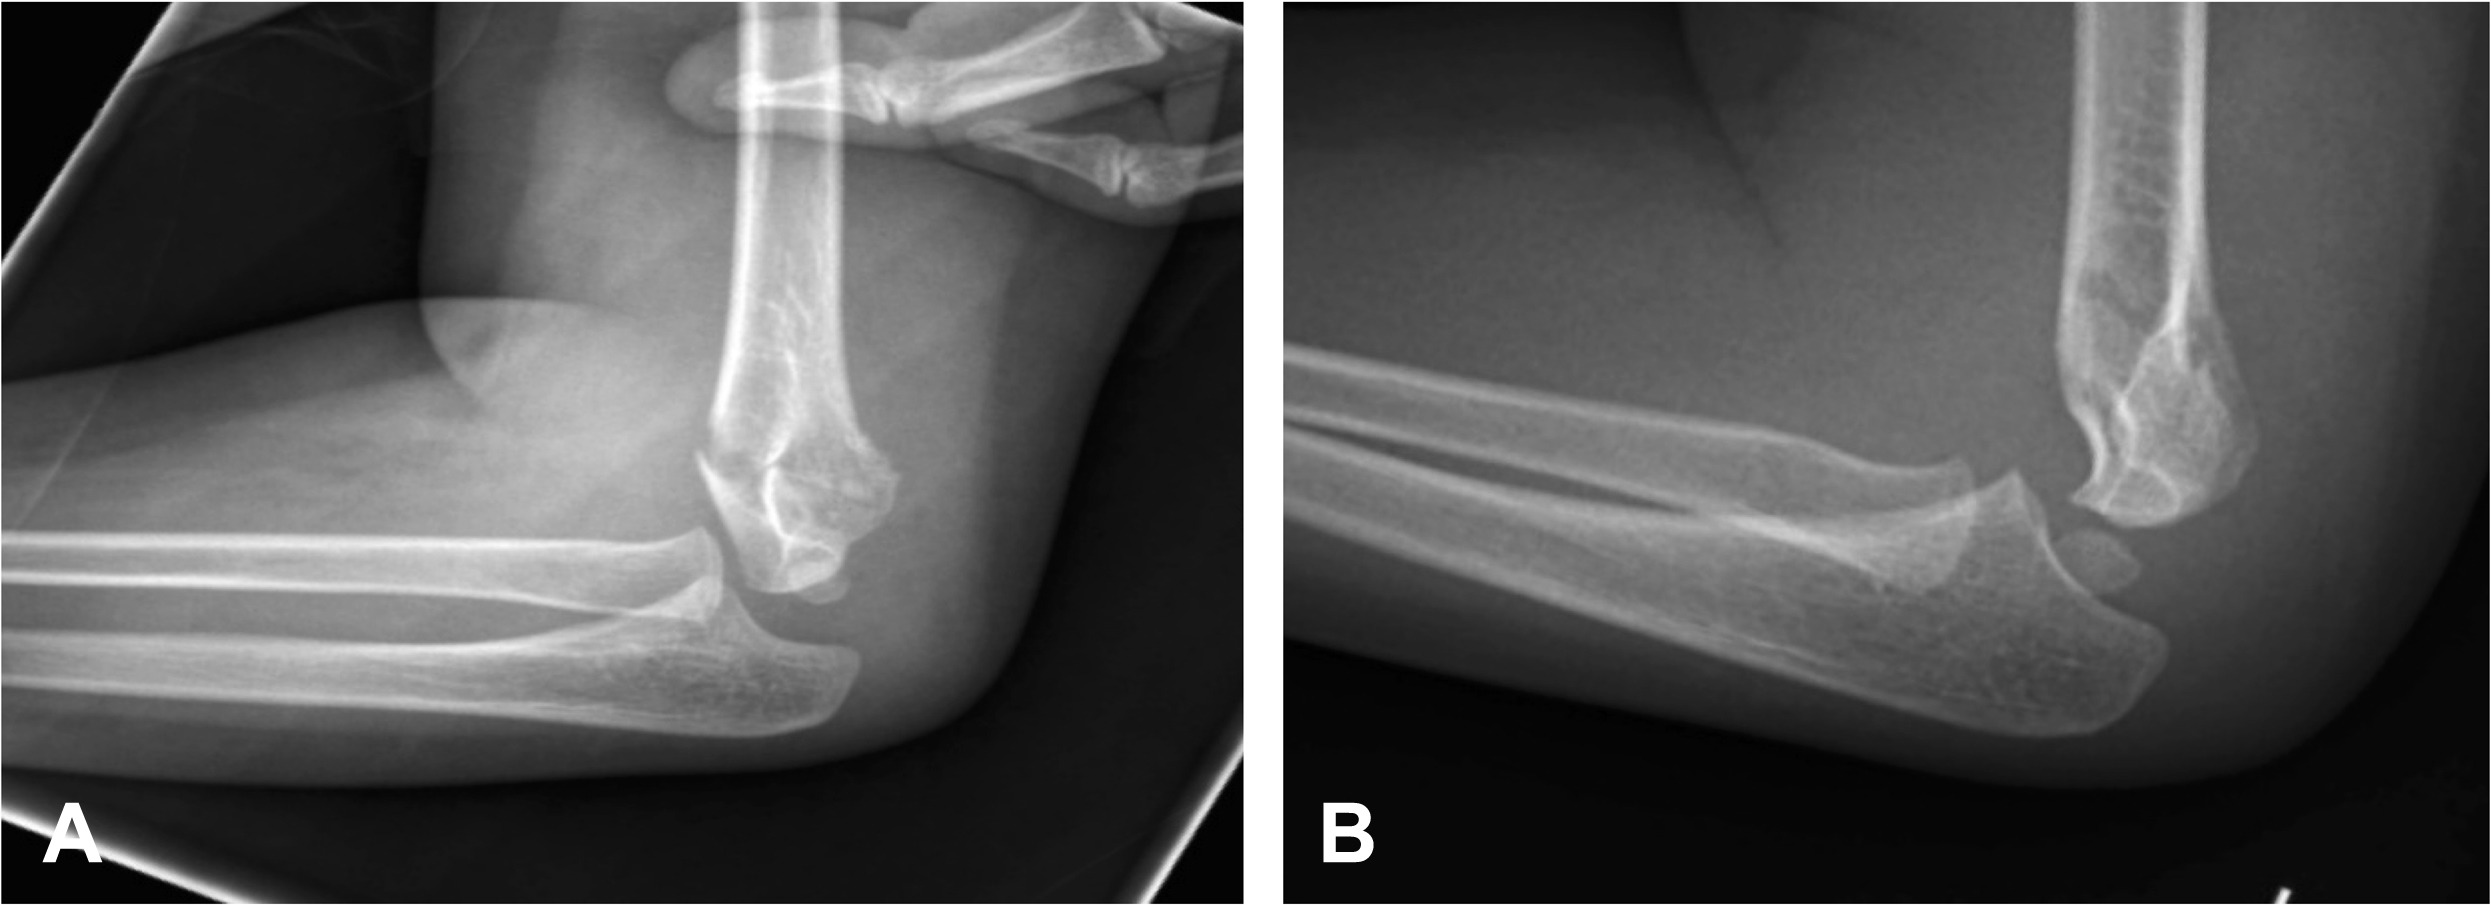

Diagnostic elbow arthroscopy can evaluate the elbow and provide a detailed diagnosi.

Arthroscopic techniques are used to restore damaged elbow cartilage.